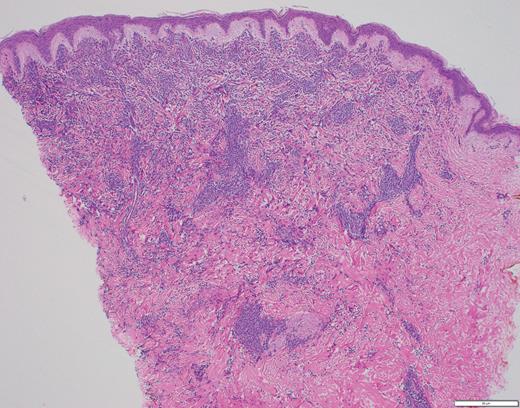

The histopathology in Case 1 demonstrated a diffuse atypical infiltrate composed of mononuclear cells extending from the epidermis to the base of the specimen with an interstitial pattern present between and among collagen bundles along with scattered mitotic figures, supporting the diagnosis of LC related to ALL (Figure 4).

Case 1 histopathology showing mononuclear cells extending from the epidermis to the base of the specimen with an interstitial pattern present between and among collagen bundles along with scattered mitotic figures. (A) Hematoxylin and eosin stain (2×); (B) hematoxylin and eosin stain (40×).